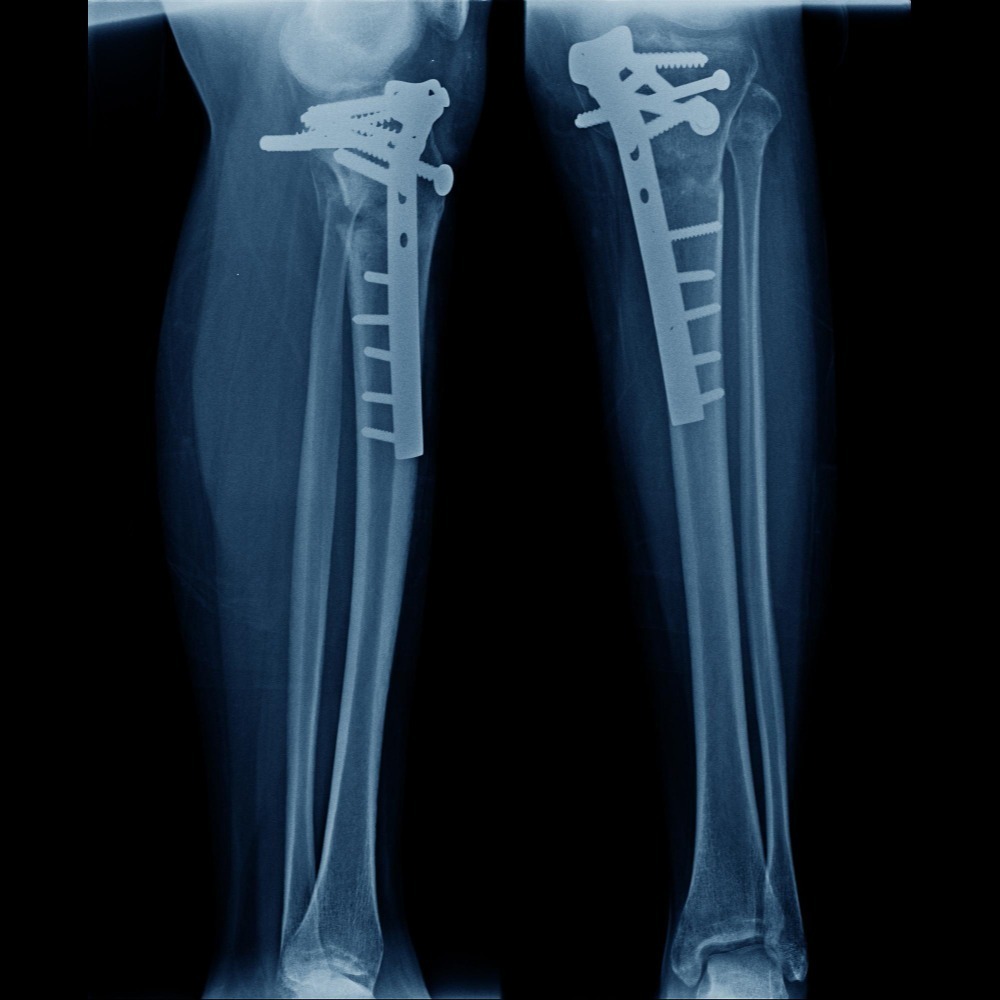

Pathological Fractures in Mumbai – Addressing the Silent Risk of Weak Bones